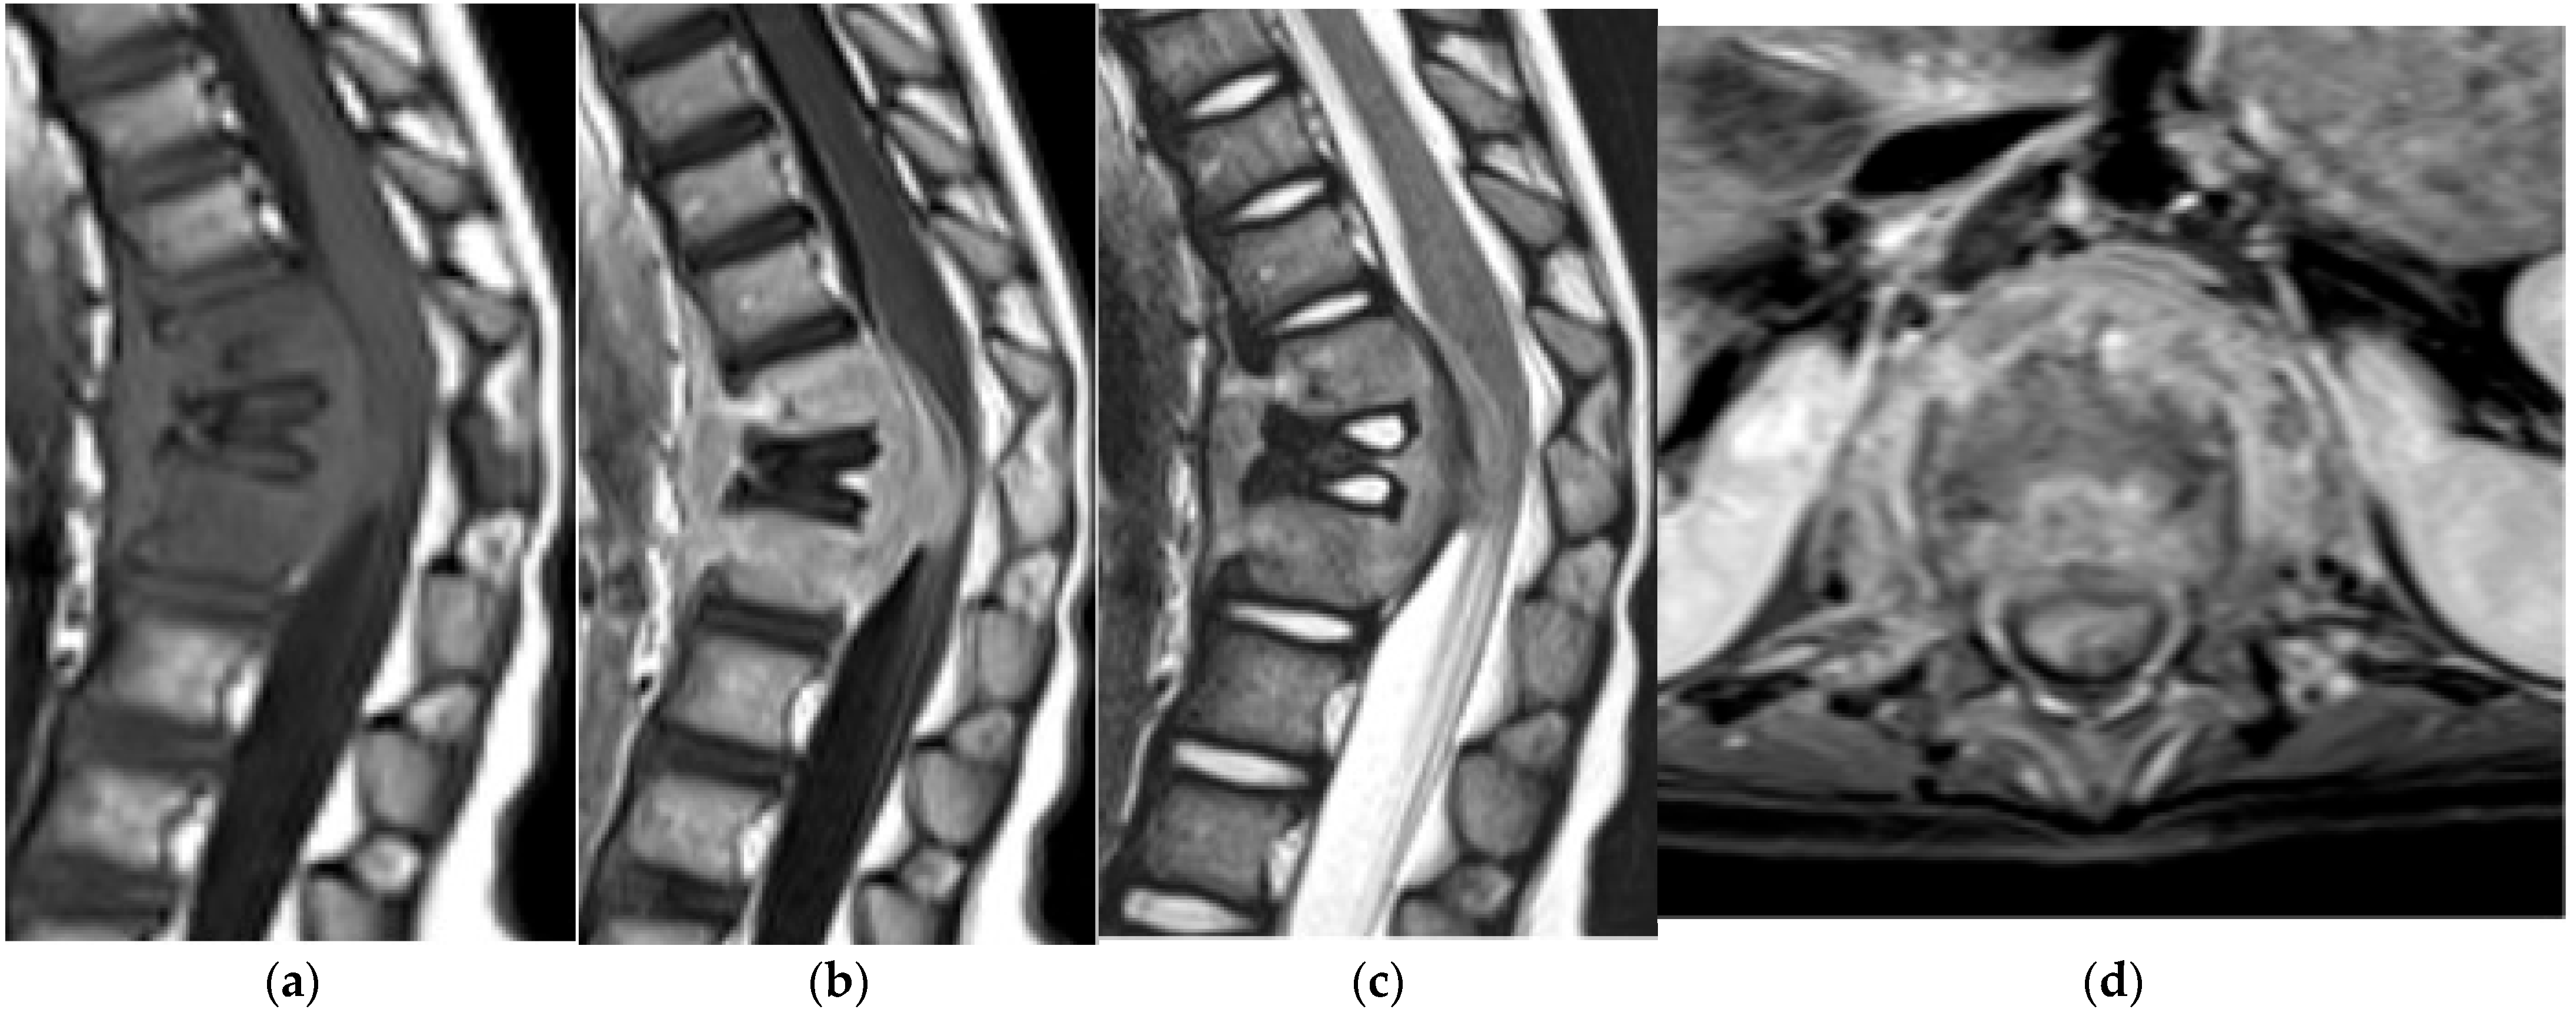

Langerhans Cell Histiocytosis